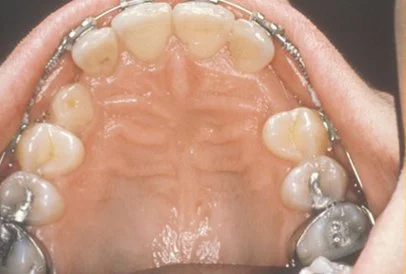

Normally, the maxillary cuspid teeth are the last of the “front” teeth to erupt into place. They usually come into place around age 13 and cause any space left between the upper front teeth to close tighter together. If a cuspid tooth gets impacted, every effort is made to get it to erupt into its proper position in the dental arch. The techniques involved to aid eruption can be applied to any impacted tooth in the upper or lower jaw, but most commonly they are applied to the maxillary cuspid (upper eye) teeth. Sixty percent of these impacted eyeteeth are located on the palatal (roof of the mouth) side of the dental arch. The remaining impacted eye teeth are found in the middle of the supporting bone, but are stuck in an elevated position above the roots of the adjacent teeth, or are out to the facial side of the dental arch.

In cases where the eyeteeth will not erupt spontaneously, the orthodontist and oral surgeon will work together to get these teeth to erupt. Each case must be evaluated on an individual basis, but treatment will usually involve a combined effort between the orthodontist and the oral surgeon. The most common scenario will call for the orthodontist to place braces on the teeth (at least the upper arch). A space will be opened to provide room for the impacted tooth to be moved into its proper position in the dental arch. If the baby eyetooth has not fallen out already, it is usually left in place until the space for the adult eyetooth is ready. Once the space is ready, the orthodontist will refer the patient to the oral surgeon to have the impacted eyetooth exposed and bracketed.

In a simple surgical procedure performed in the surgeon’s office, the gum on top of the impacted tooth will be lifted up to expose the hidden tooth underneath. If there is a baby tooth present it will be removed at the same time. Once the tooth is exposed, the oral surgeon will bond an orthodontic bracket to the exposed tooth. The bracket will have a miniature gold chain attached to it. The oral surgeon will guide the chain back to the orthodontic arch wire where it will be temporarily attached. Sometimes the surgeon will leave the exposed and impacted tooth completely uncovered by suturing the gum up high above the tooth, or making a window in the gum covering the tooth. Most of the time the gum will be returned to its original location and sutured back with only the chain remaining visible as it exits a small hole in the gum.